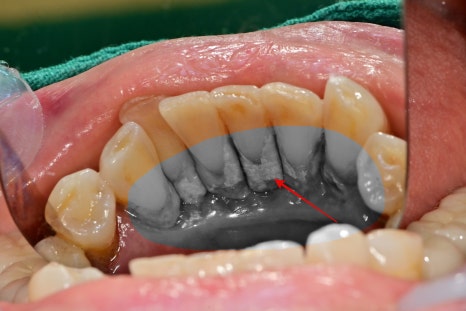

아래 앞니 쪽 안쪽으로 치석이 많이 쌓여있었는데

주변 잇몸이 많이 부어있고, 치아에 동요도가 생긴 상태였습니다.

다행히염증은 많이 진행된 상태는 아니라

스케일링 후 잇몸치료를 진행하여 건강하게 회복되었습니다.

일반적으로 아래턱 앞니 안쪽은

침샘과 가깝고, 칫솔질의 각도가 용이하지 않기 때문에

치석이 잘 쌓이는 환경입니다.

사진과 같이 치석이 쌓이며

더 이상 치아가 지지를 못 받을 정도로 치주염이 진행된 상태입니다.

이 정도로는 잇몸치료를 하더라도 치아의 흔들림을 잡아줄 수 없기 때문에

해당 케이스는 발치를 진행했던 경우입니다.